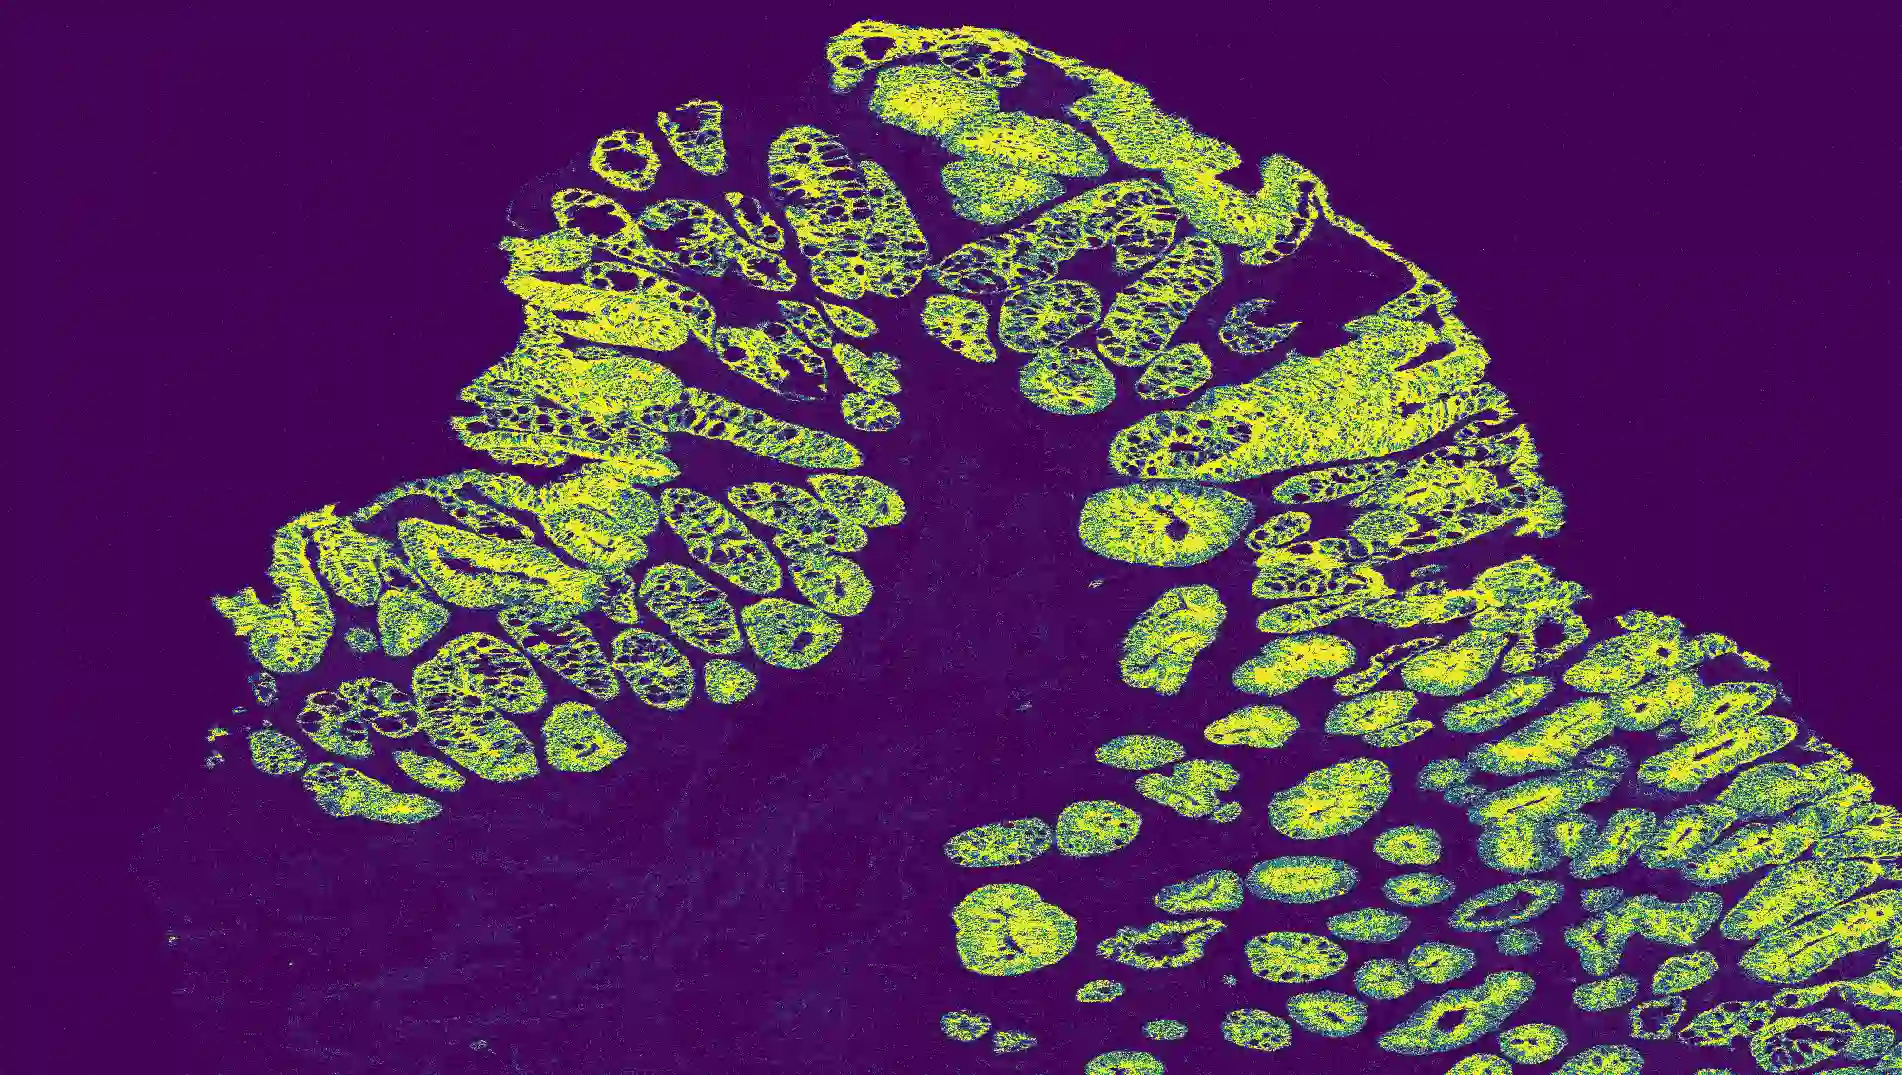

The usage of chemical imaging technologies is becoming a routine accompaniment to traditional methods in pathology. Significant technological advances have developed these next generation techniques to provide rich, spatially resolved, multidimensional chemical images. The rise of digital pathology has significantly enhanced the synergy of these imaging modalities with optical microscopy and immunohistochemistry, enhancing our understanding of the biological mechanisms and progression of diseases. Techniques such as imaging mass cytometry provide labelled multidimensional (multiplex) images of specific components used in conjunction with digital pathology techniques. These powerful techniques generate a wealth of high dimensional data that create significant challenges in data analysis. Unsupervised methods such as clustering are an attractive way to analyse these data, however, they require the selection of parameters such as the number of clusters. Here we propose a methodology to estimate the number of clusters in an automatic data-driven manner using a deep sparse autoencoder to embed the data into a lower dimensional space. We compute the density of regions in the embedded space, the majority of which are empty, enabling the high density regions to be detected as outliers and provide an estimate for the number of clusters. This framework provides a fully unsupervised and data-driven method to analyse multidimensional data. In this work we demonstrate our method using 45 multiplex imaging mass cytometry datasets. Moreover, our model is trained using only one of the datasets and the learned embedding is applied to the remaining 44 images providing an efficient process for data analysis. Finally, we demonstrate the high computational efficiency of our method which is two orders of magnitude faster than estimating via computing the sum squared distances as a function of cluster number.